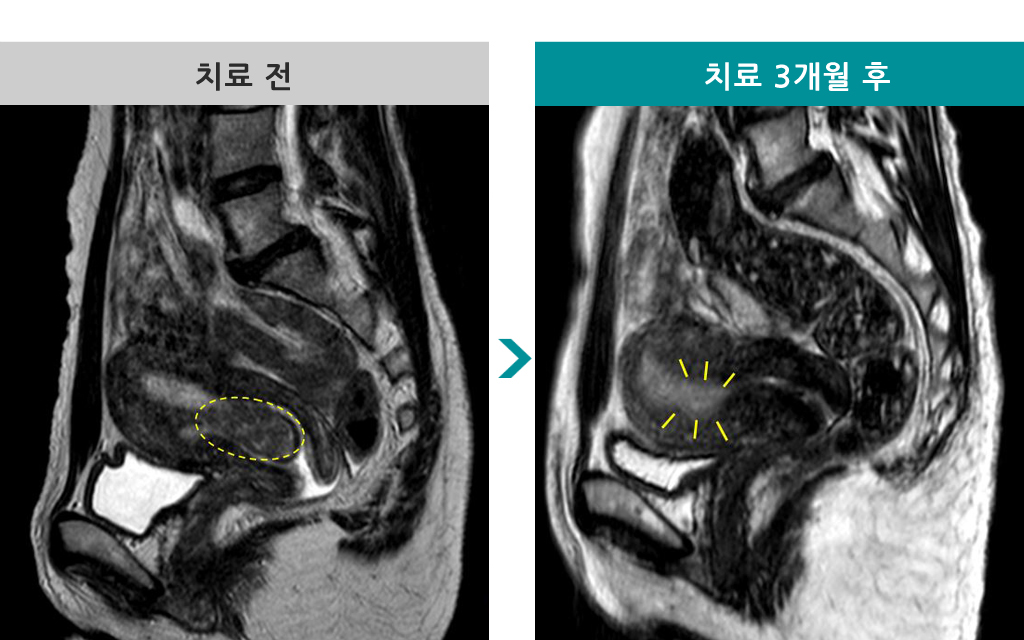

49세 [자궁선근증 색전술] 전후 MRI사진 비교